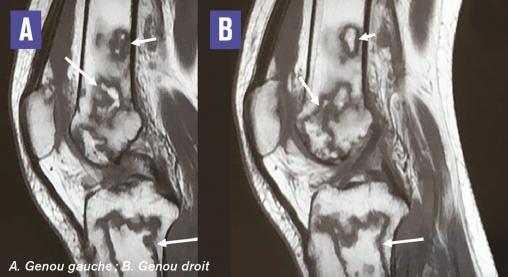

Cette femme de 24 ans consultait pour des gonalgies bilatérales mécaniques évoluant depuis 3 mois. La patiente était maigre (IMC à 14), sa marche était précautionneuse, sans trouble neurologique. L’interrogatoire notait un tabagisme chronique depuis l’âge de 18 ans et une corticothérapie en automédication à raison de 40 mg/j pendant 18 mois. La fonction articulaire était bonne, douloureuse à la mobilisation des genoux. Il n’y avait pas d’épanchement articulaire ni de signes en relation avec une maladie de système ou de surcharge. La radiographie notait quelques plages d’ostéocondensation inhomogènes des condyles fémoral et tibial droits, et une déminéralisation osseuse hétérogène des deux condyles fémoraux et du plateau tibial gauche (fig. 1 ). L’IRM montrait des images d’os dans l’os caractéristiques d’infarctus osseux (fig. 2 ). Le bilan biologique et l’échographie abdominale étaient normaux. Les autres causes ayant été exclues en raison de la normalité des explorations, les infarctus osseux étaient liés à la corticothérapie au long cours.